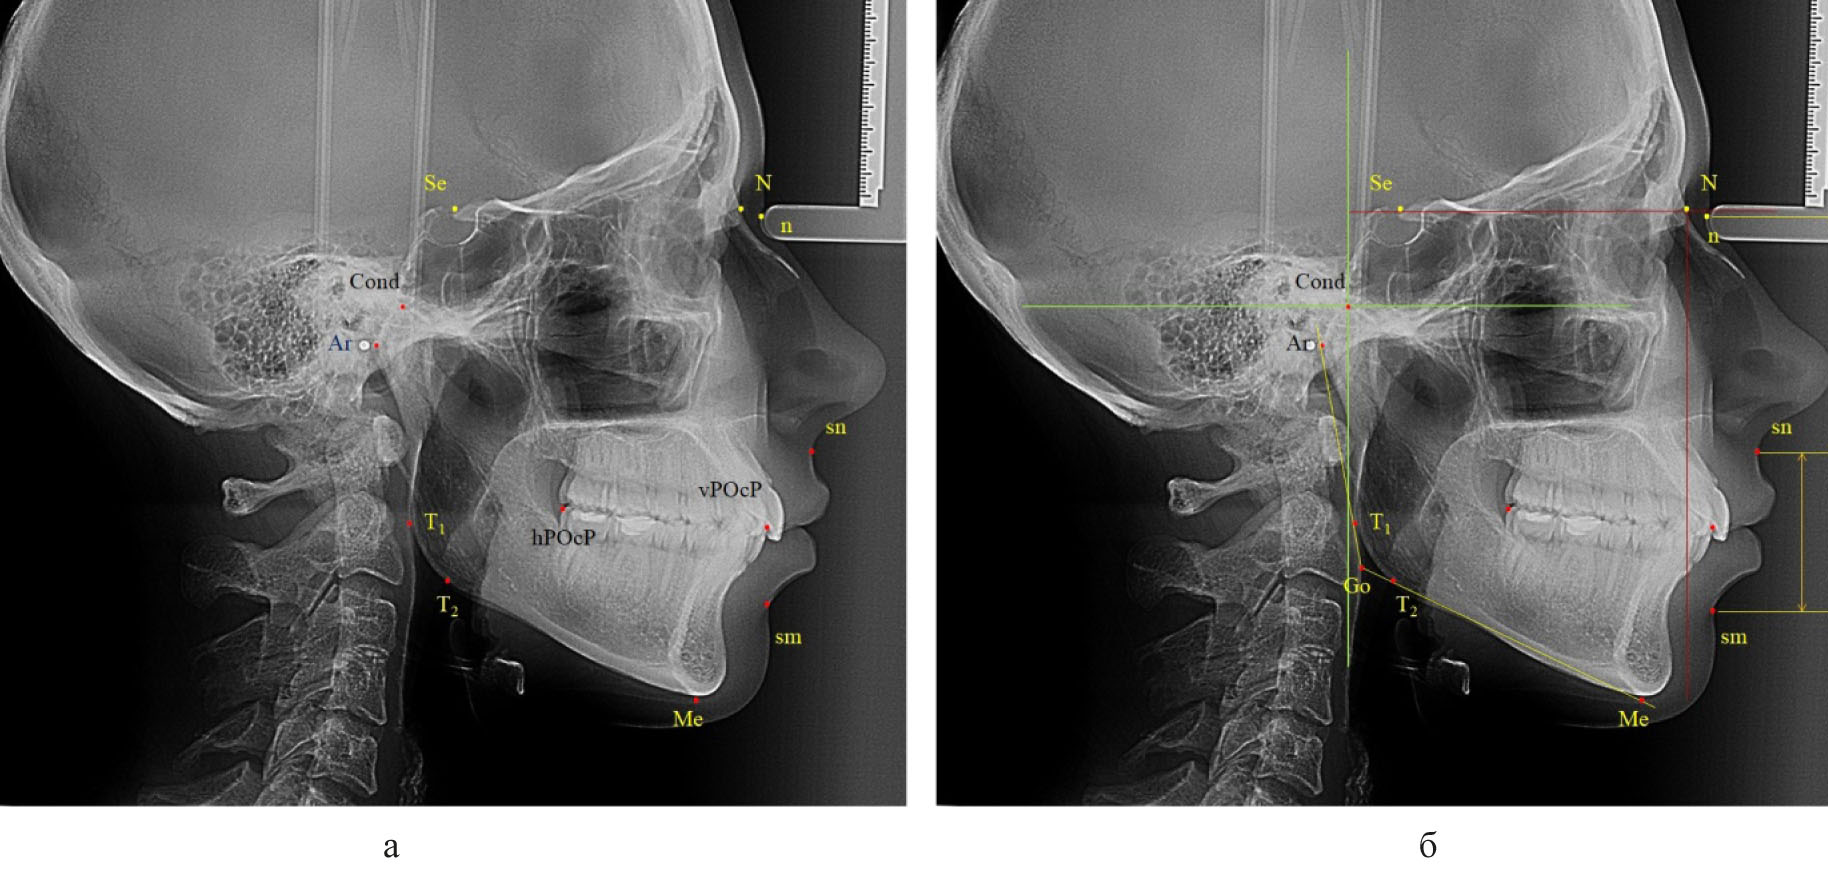

Далее проводили построение суставного круга, радиусом которого было расстояние от точки «Cond» до задней окклюзионной точки «hPOcP» (рис. 3).

Рис. 3. Основные точки (а) особенности построения суставного круга и диагностических линий (б) для построения окклюзионной плоскости

Следует отметить, что окружность пересекала линию «Cond-Mx» и делила ее на два неравных отрезка. При этом расстояние от точки «Cond» до пересечения с окружностью было в 1,5 раза меньше размера «Cond-Mx», что может быть использовано в качестве ориентира построения суставного круга при отсутствии зубов жевательных сегментов или при аномалиях положения вторых моляров.

Касательная линия к нижней части суставного круга, проведенная из точки мандибулярного ориентира «Mn», как правило, была параллельна окклюзинной линии вне зависимости от типологических особенностей роста лица и челюстных костей.